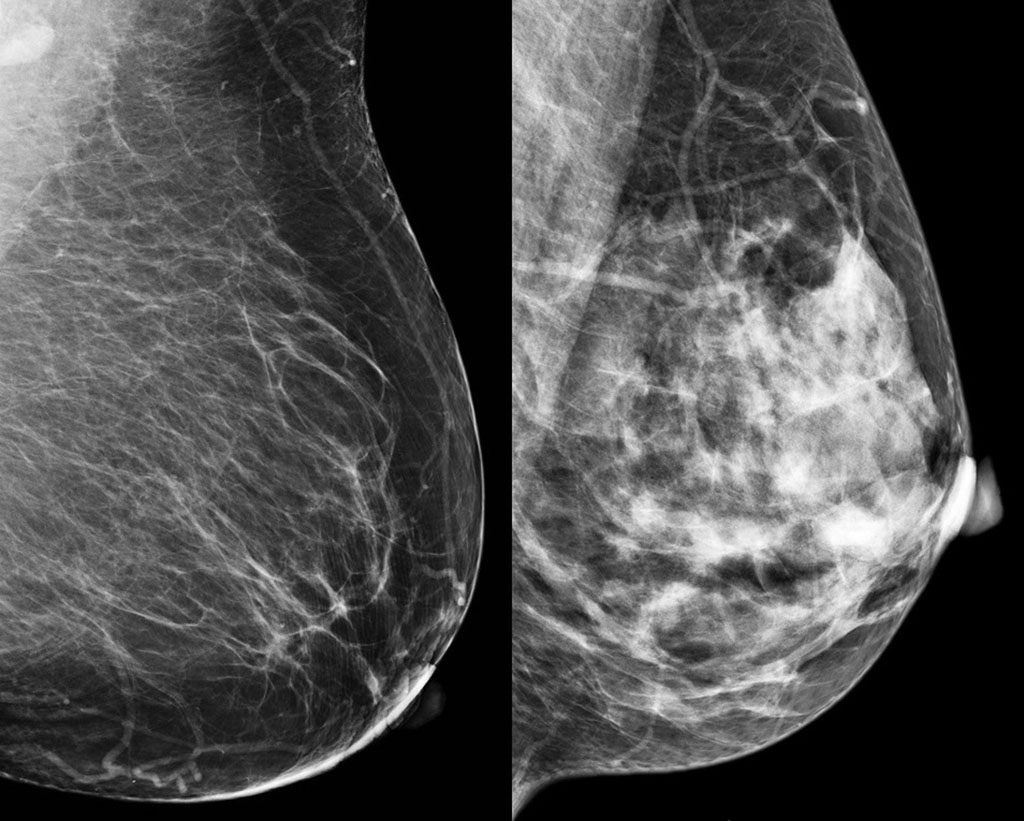

와... 근데 진짜 텅비었네... 한국인 검사결과는 저렇지 않자나...x

살면서 저렇게 텅 빈거 처음봄…